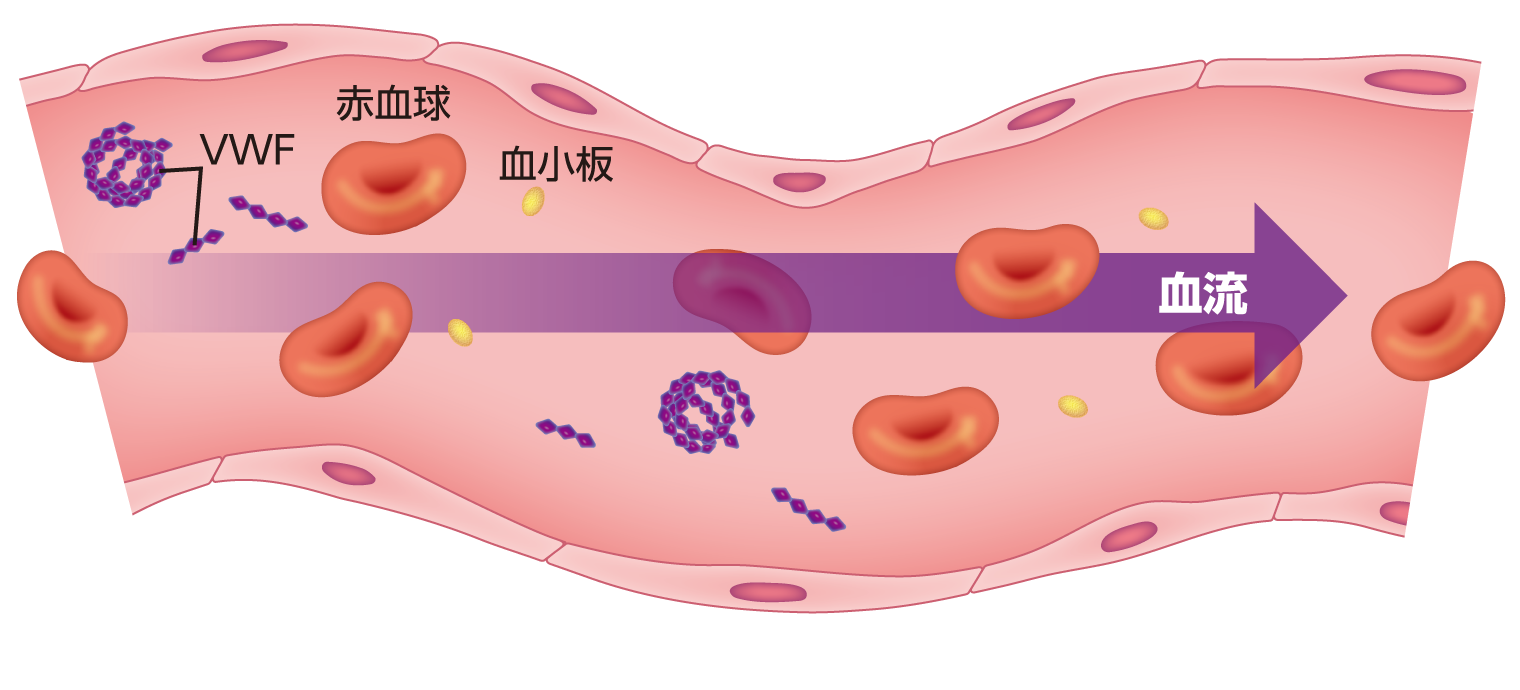

TTPとはTTPについてTTPについて知っておきたいこと Understanding TTP サノフィ株式会社 Sanofi。

血液凝固と線溶こんにちは✨薬剤師ロクガツです。 今回は血液凝固と線溶系についてのまとめです。 止血機構に関わる ✔︎血友病✔︎DIC 播種性血管内凝固✔︎ITP 特発性血小板紫斑病✔︎TTP 血栓性血小板減少性紫斑病の病態もザックリまとめました。